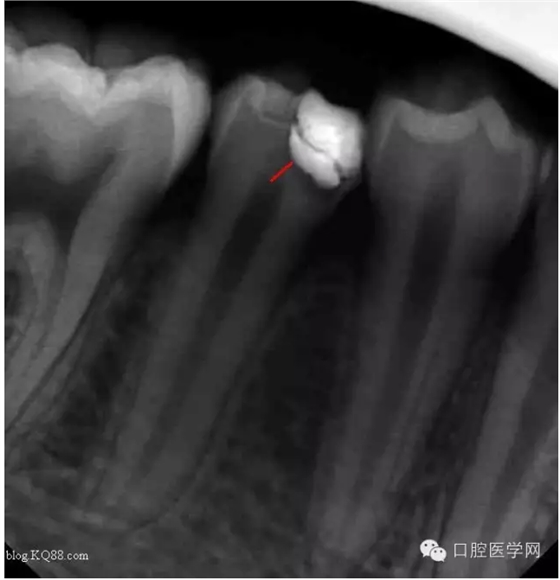

病人是我的助手,牙齒酸痛一周。吃冷熱時(shí)加重。無(wú)自發(fā)痛。先看看牙片

根據(jù)主訴:一過(guò)性冷熱痛無(wú)自發(fā)痛,X線:根尖無(wú)明顯改變應(yīng)診斷為深齲。小伙子平時(shí)愛(ài)吃冷飲最近冷飲是不敢吃了。

去腐,備洞。發(fā)現(xiàn)已經(jīng)露髓。根據(jù)年輕恒牙保存活髓治療原則。選擇直接蓋髓術(shù)?;颊呤俏业闹种辣4婊钏璧闹匾裕灾皇亲隽撕?jiǎn)單的溝通。如果其他病人遇到這種情況術(shù)前溝通很重要。首先灌輸保髓的重要性,告知術(shù)后反應(yīng),以避免不必要的麻煩